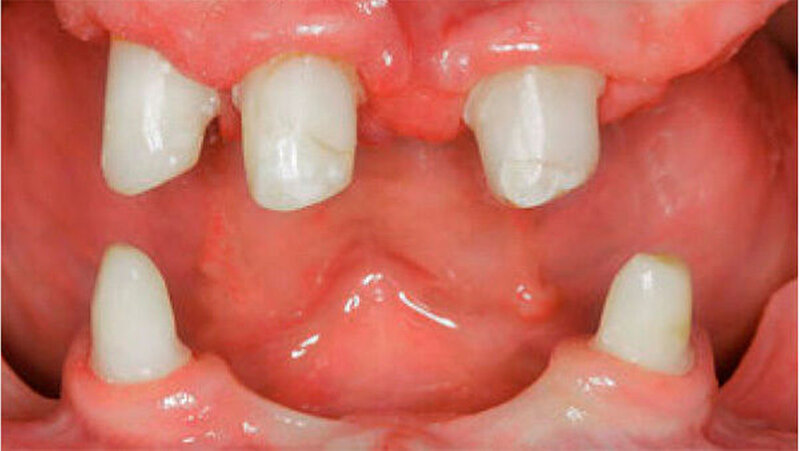

Der bei Behandlungsbeginn 14-jährige Patient war mit einer neun beziehungsweise fünfjährigen Prothese im Unter- beziehungsweise Oberkiefer versorgt (Abb. 2 und 3). Die angelegten Zapfenzähne 12, 11 und 21 waren bereits mehrfach konservierend restauriert und wiesen diverse Stellen mit Sekundärkaries auf. Die Kronenränder der Zähne 33 und 43 waren deutlich sondierbar. Der Kieferkamm im Unterkiefer war aufgrund der fehlenden Zahnanlagen sehr schmal (Abb. 4 bis 6). Die Panoramaschichtaufnahme zeigte das reduzierte vertikale Knochenangebot (Abb. 7). Da die Vitalerhaltung der wenigen Restzähne aufgrund des jungen Alters des Patienten unbedingt anzustreben war, wurde als Behandlungsziel im Ober- und Unterkiefer eine Versorgung mit Hybridprothesen, retiniert auf Teleskopkronen, festgelegt.

Um die Realisierbarkeit des Therapieziels zu überprüfen, erfolgte im Vorfeld eine diagnostische Aufstellung der Prothesenzähne im Ober- und im Unterkiefer, was eine adäquate Analyse des intra- und intermaxillären Platzangebots ermöglichte (Abb. 8 bis 10). Nun wurden die Pfeilerzähne für die Rekonstruktion mit Teleskopkronen präpariert (Abb. 11). Die individuellen Abformlöffel für die definitive Abformung entsprachen einem Duplikat der diagnostischen Aufstellungen des Ober- und Unterkiefers aus durchsichtigem Kunststoff. Dies ermöglichte gleichzeitig die Montage der Meistermodelle und die Übertragung der Gesamtaufstellung auf das Meistermodell.